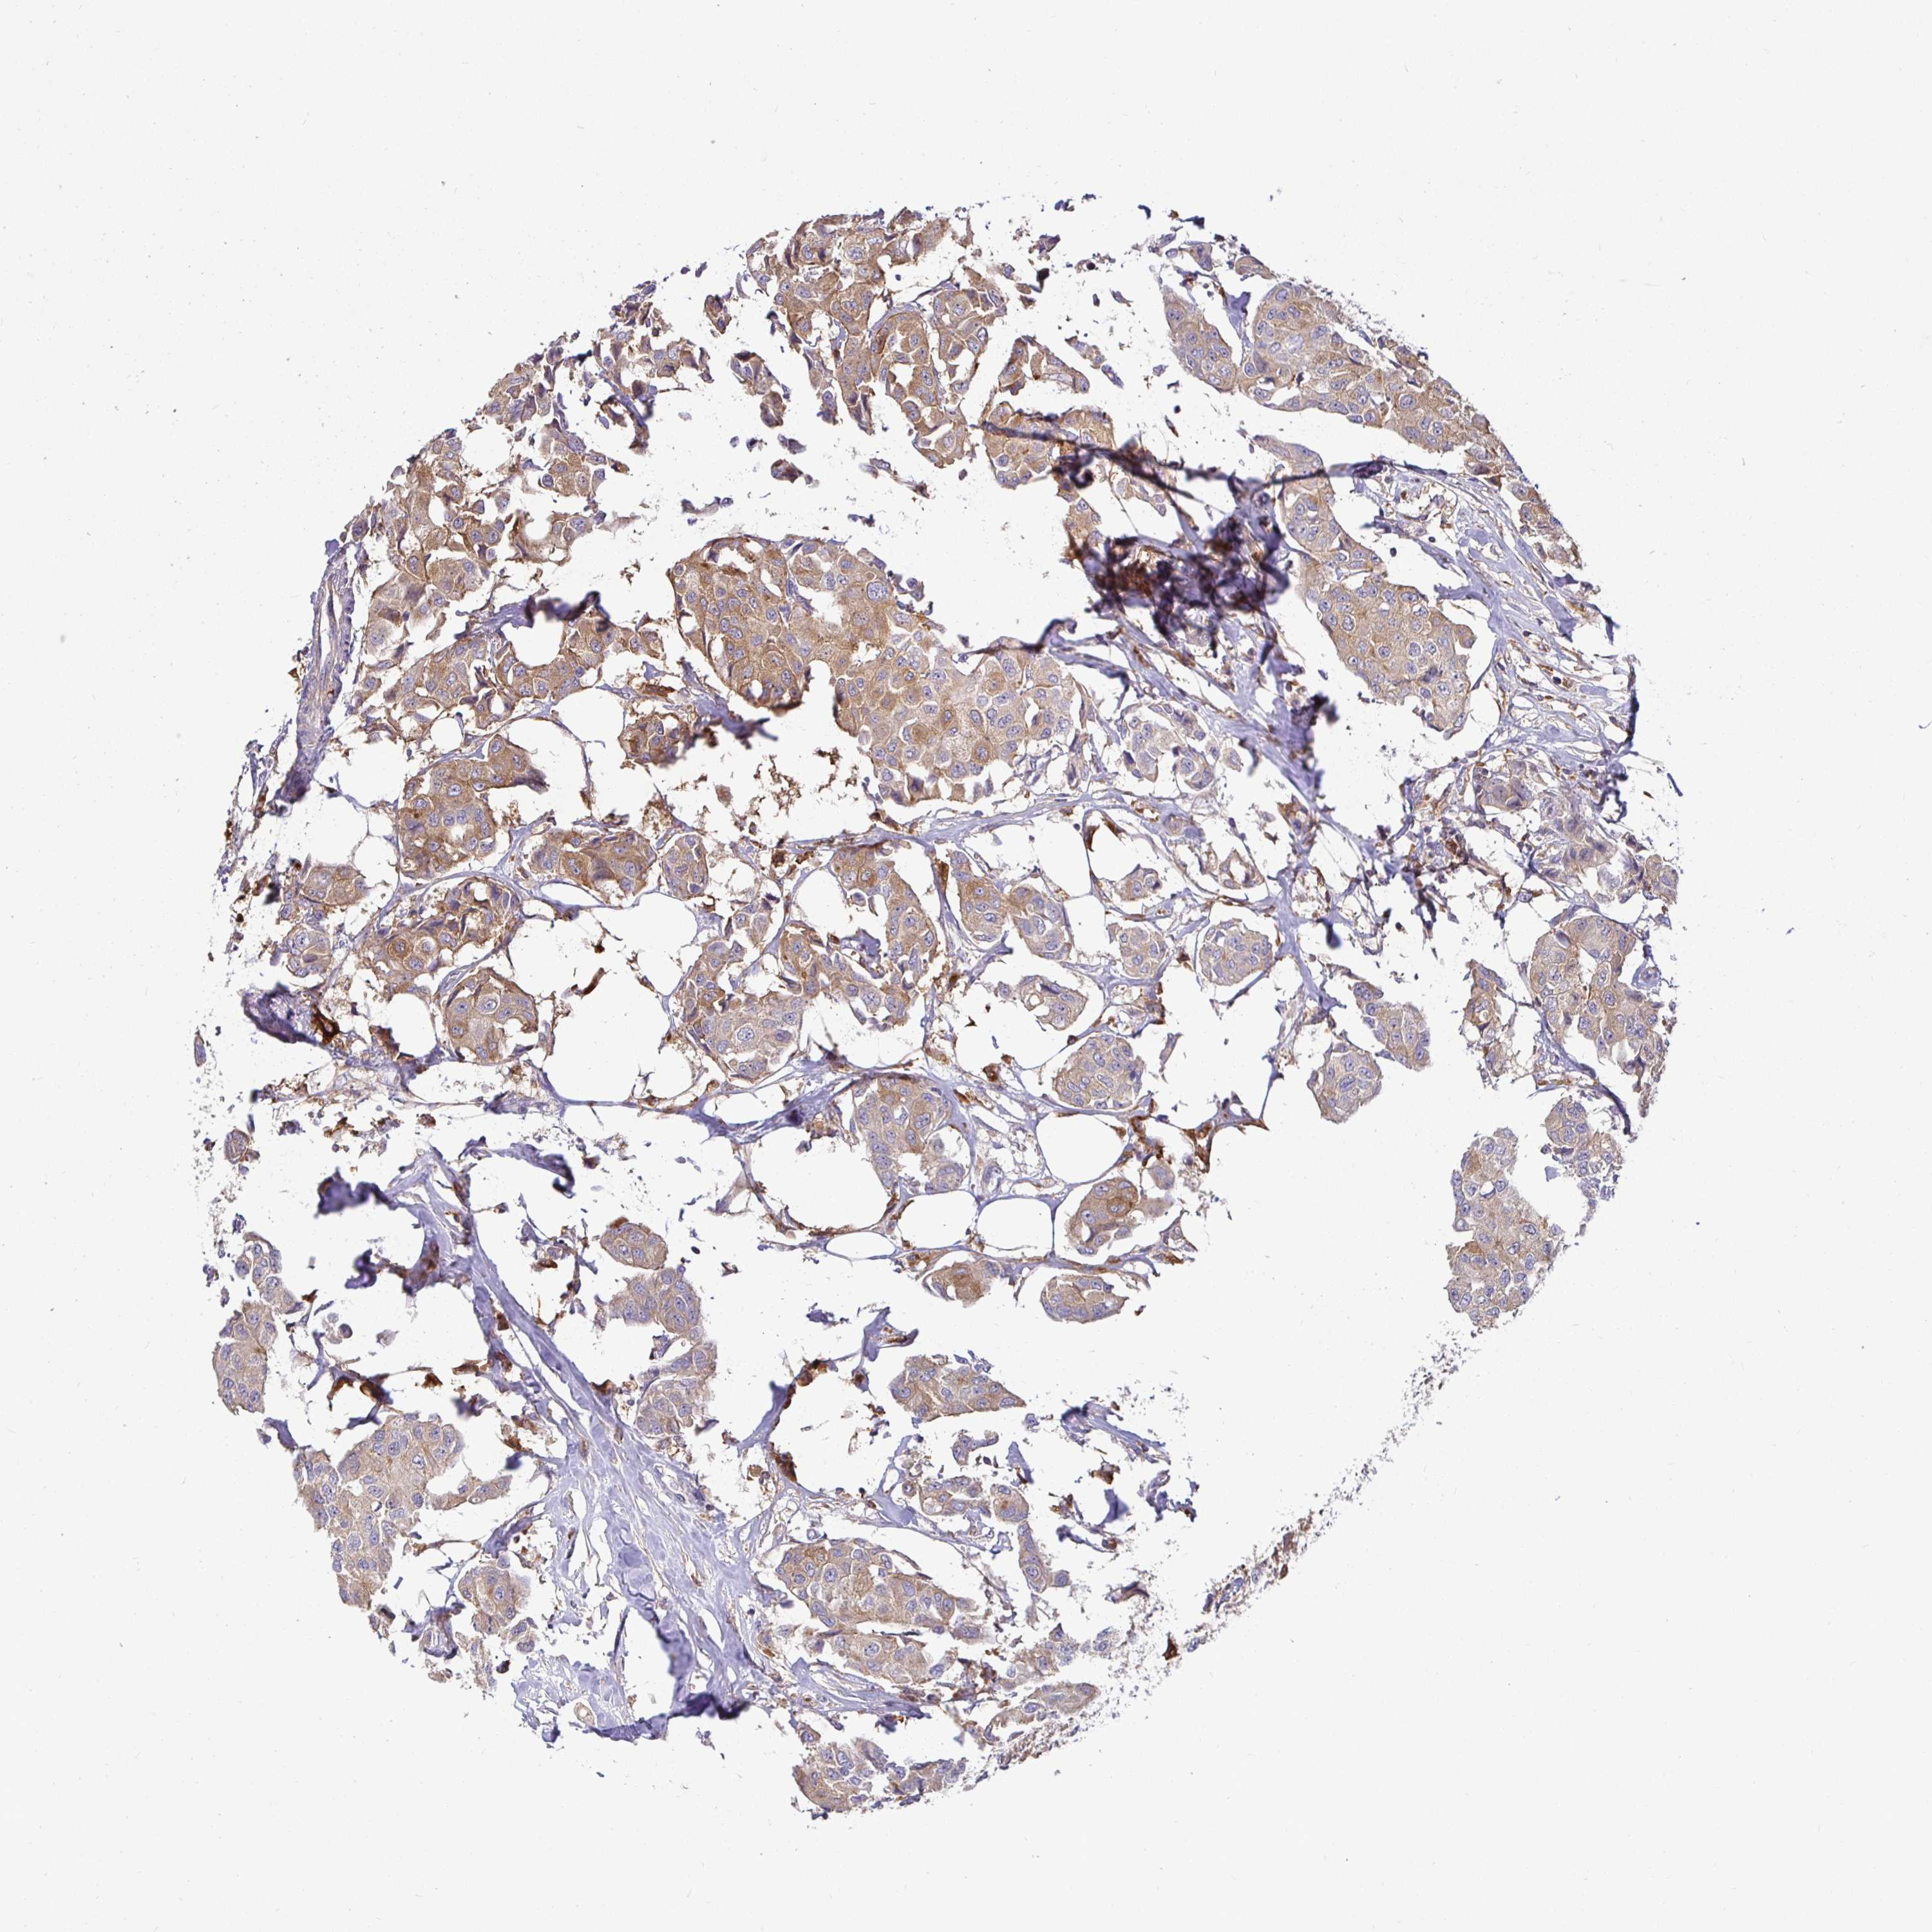

BRCA TCGA BRCA VALIDATION PROTEIN EXPRESSION

ANTIBODIES

AND

VALIDATION